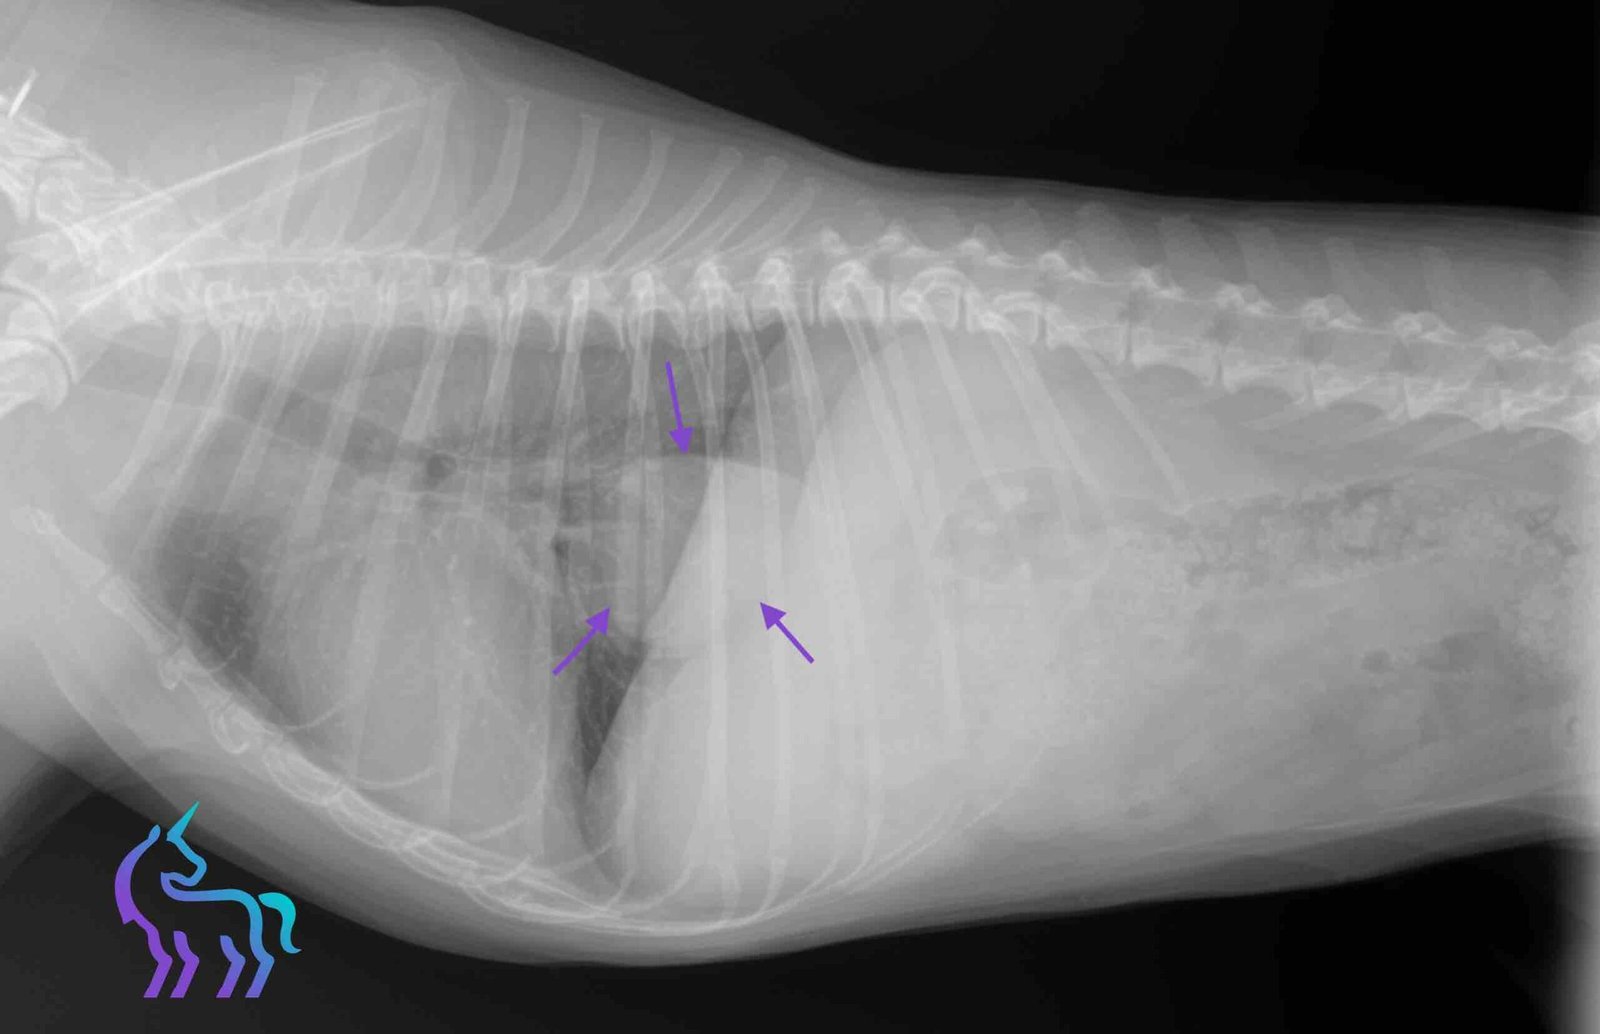

Cas cliniques en radiographies

Explorez nos diagnostics par imagerie à travers des cas concrets rencontrés au sein de la clinique.